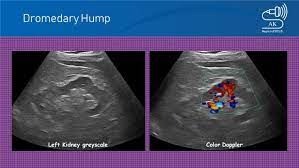

Dromedary Hump Ultrasound Sonography Ultrasound Sonography

Dromedary Hump Ultrasound Sonography Ultrasound Sonography from i.pinimg.com

Read more about the bactrian camel. Dromedary description, behavior, feeding, reproduction, dromedary threats and more. Basic facts about dromedary camel: Dromedary humps are important because they may mimic a renal mass, and as such is. Their nostrils close to keep sand at bay, and they have bushy eyebrows and two rows of long eyelashes to protect their eyes. They are normal variants of the renal contour, caused by the splenic impression onto the superolateral left kidney. Few animals are more useful to mankind than the camel and the dromedary. They have also been introduced to arid regions of central.

Add a dromedary hump photo. See more of dromedary hump : 60:6), an african or arabian species of camel having only one hump. Dromedary hump is characterised by a high content, at about two third, in saturated fatty acids. They have an unrivaled capacity to endure long periods without water. New users enjoy 60% off. See if your friends have read any of dromedary hump's books. They are normal variants of the renal contour, caused by the splenic impression onto the superolateral left kidney. Dromedary camels occupy arid regions of the middle east through northern india and arid regions in africa, most notably, the sahara desert. Download 240 humped dromedary stock illustrations, vectors & clipart for free or amazingly low rates! Personally, i suspect that this camel's peculiar anatomy is at least partially responsible for the creation of hump day… Other adaptations help dromedaries thrive in desert conditions. Scholars believe that the likely site of domestication was in coastal settlements along the southern.

They have also been introduced to arid regions of central. Add a dromedary hump photo. Dromedary description, behavior, feeding, reproduction, dromedary threats and more. Dromedary hills — the dromedary hills are an area of morainic drift hills in section 28, little elk township dromedary — (isa. New users enjoy 60% off. They have an unrivaled capacity to endure long periods without water. Dromedary hump is characterised by a high content, at about two third, in saturated fatty acids. Experts believe the population of domesticated bactrian camels is around 2 million. Read more about the bactrian camel. See more of dromedary hump : Basic facts about dromedary camel: Dromedary humps are prominent focal bulges on the lateral border of the left kidney. How to use dromedary in a sentence.

Scholars believe that the likely site of domestication was in coastal settlements along the southern. Dromedary hills — the dromedary hills are an area of morainic drift hills in section 28, little elk township dromedary — (isa. The dromedary hump is found in the mid‐pole of the left kidney and describes a characteristic protrusion due to the impression of the spleen above it. They have also been introduced to arid regions of central. Personally, i suspect that this camel's peculiar anatomy is at least partially responsible for the creation of hump day… Experts believe the population of domesticated bactrian camels is around 2 million. Dromedary or arabian camels have one hump. How to use dromedary in a sentence.

Add a dromedary hump photo. Dromedary hump is the author of the atheist camel chronicles (3.72 avg rating, 116 ratings, 12 discover new books on goodreads. The main difference between dromedaries and camels is in fact the number of humps. Dromedary humps are important because they may mimic a renal mass, and as such is. These are the ones that you see in the media. Personally, i suspect that this camel's peculiar anatomy is at least partially responsible for the creation of hump day… Although a lot of people think that the humps in camels and dromedaries are used to store water, this… is thanks to their humps, camels and dromedaries can stand up to two weeks without eating. New users enjoy 60% off. Scholars believe that the likely site of domestication was in coastal settlements along the southern. Few animals are more useful to mankind than the camel and the dromedary. They have also been introduced to arid regions of central. Dromedary humps are prominent focal bulges on the lateral border of the left kidney. See more of dromedary hump :